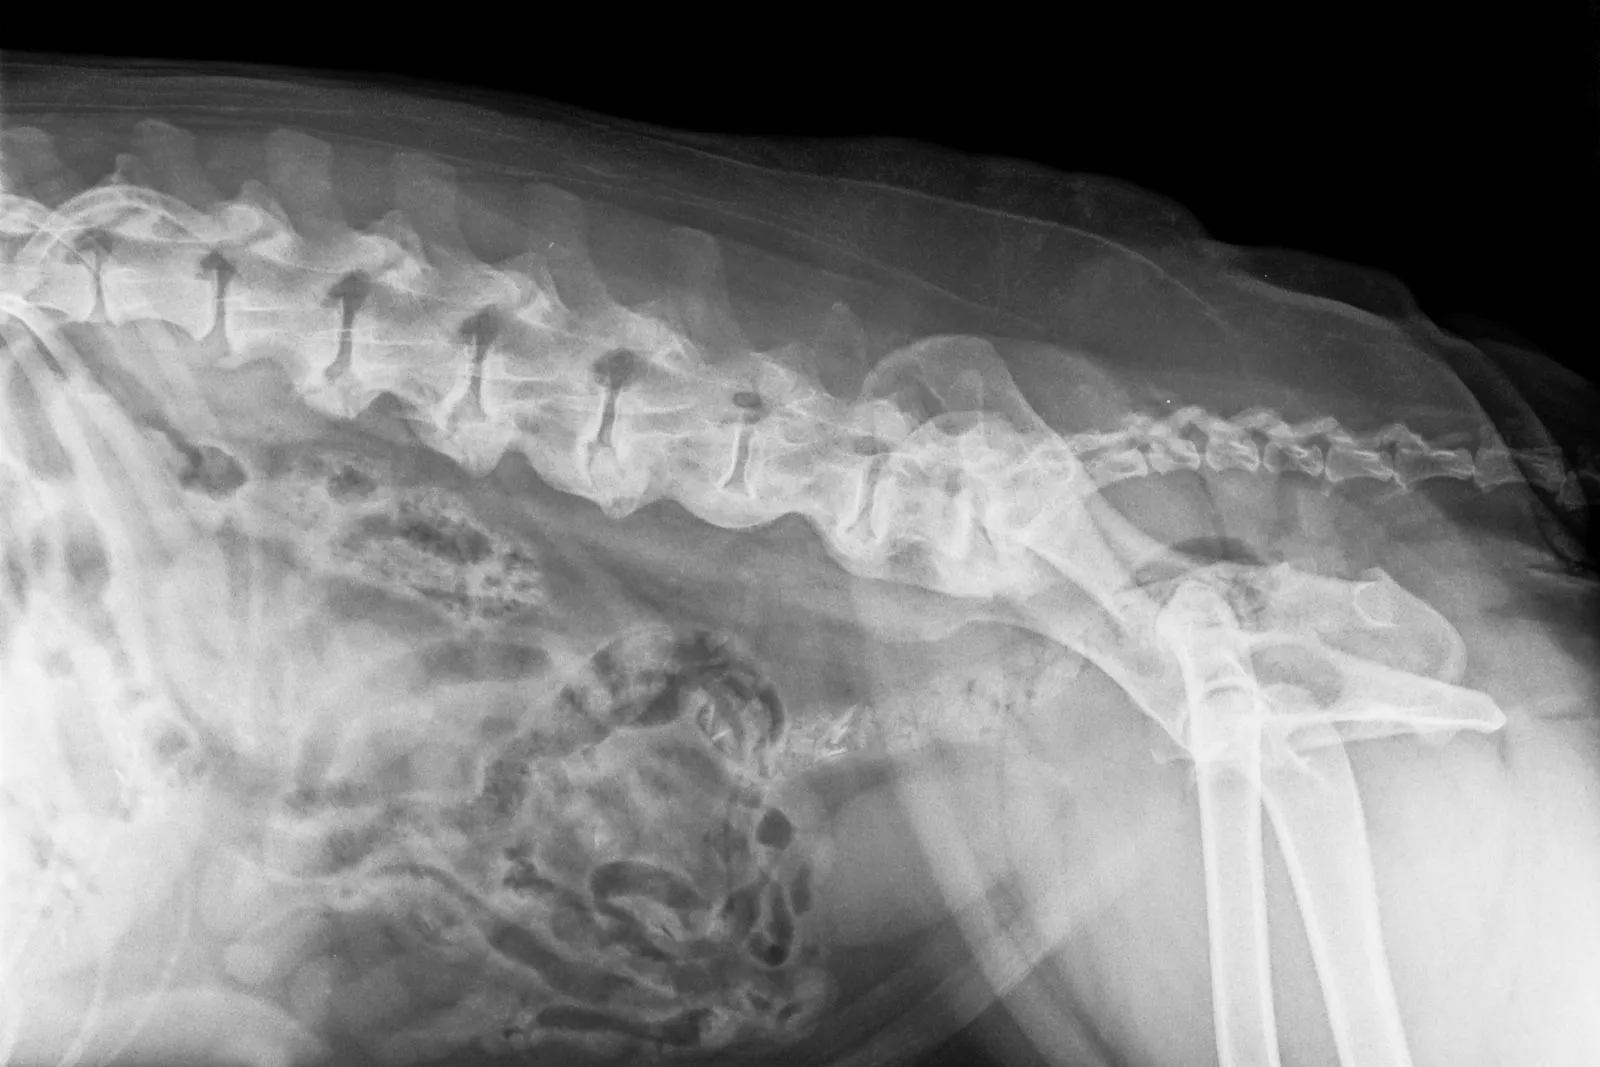

Röntgenopname van spondylose bij de hond © Henk Vrieselaar / stock.adobe.com

Deze röntgenopname van een oudere hond toont een ernstige spondylosis deformans, gekenmerkt door botuitsteeksels langs de botrand van de wervelkolom.

Voor een nauwkeurigere beoordeling van de wervelkolom heeft uw dierenarts vervolgens een röntgenapparaat nodig. Op de röntgenfoto kan de arts de botaanwas aan de wervels meestal goed zien en andere oorzaken uitsluiten. Daarnaast helpt het beeld om het aantal en de ernst van de spondyloses in te schatten.